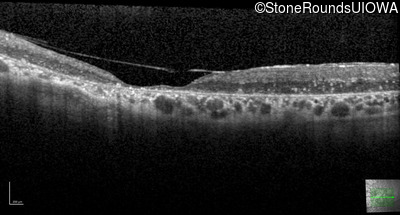

This 41 year old man first came to medical attention at age 18 months when exotropia and amblyopia of his right eye were discovered. At age 11 vitreous strands and retinal vascular sheathing were seen. He has had poor night vision and constricted visual fields since his late teens. Later, at age 44 a traction retinal detachment was noted in his left eye and was treated with a scleral buckle.

Age at visit: 41 years